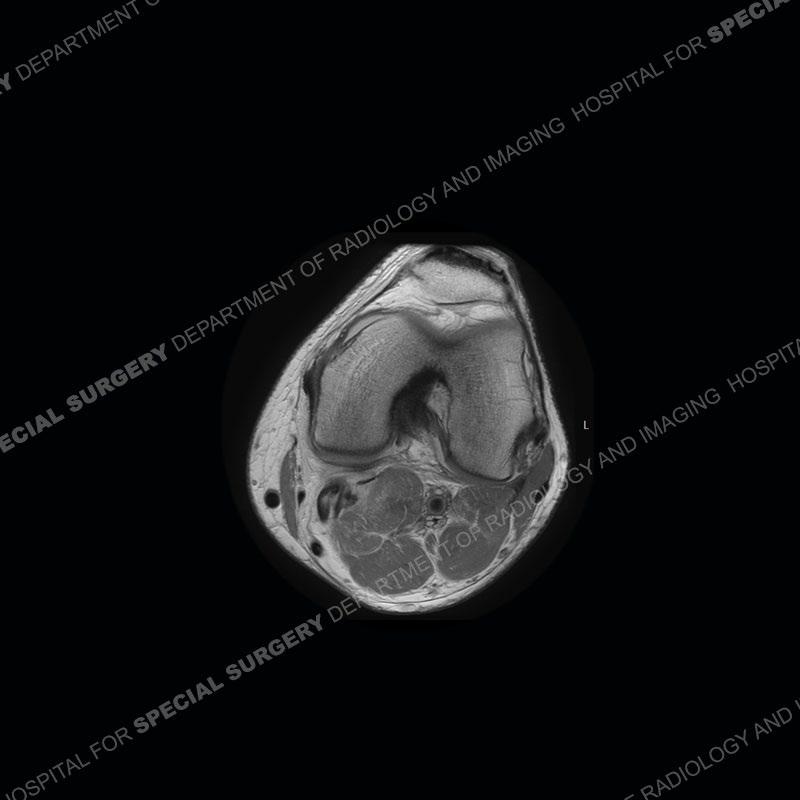

Findings

The radiographs show degenerative change of the medial compartment and a varus knee, but they are not germane to this case. No acute bony injury is present. The MRI shows edema of the posterior medial knee/soft tissue and a focal area of a partially disrupted low signal structure. The details are kept at a minimum in the findings of this case on purpose.

Diagnosis: Partial Disruption Medial Head Gastrocnemius (MHG)

The findings were kept purposefully vague as identifying the structures early on takes away a lot of the diagnosis. An uncommon entity and one of which we do not see a lot. Enthesopathic changes and tendinosis are seen as are distal MHG injuries, but proximal tears are rarely present. This case highlights a number of points. One, it almost always comes down to anatomy. Perhaps not a structure we normally spend too much time on, except save for diagnosing a Baker’s cyst, but knowing where this structure and all structures exist in all three planes is imperative. Second, when you think you are making a “call” or finding that you have never made before, step back and think is this just the abnormal presentation of a common pathology. That situation arises much more frequently. Third, if you look at it once, twice, and probably a third time and are confident in your odd or very rare diagnosis, stick to your guns. Especially, when it comes down to anatomic structures, the proof will be in the images.

Fourth, use all imaging planes and different pulse sequences to make your diagnosis. The edema highlighted in this case can be seen as the obscuration of fat on the PD images but is much easier to perceive as the high signal on the IR pulse sequences. The actual disruption of the MHG myotendinous junction is only able to be seen on the axial images. On the sagittal and coronal images, we get a sense something is wrong but hard to be exact. Lastly, when you look at a study and something just seems off (as I would say the sagittal and coronal images do with that dark band of tissue posteriorly), listen to yourself and go through the study slowly and meticulously. Most of the time you will find you were right, and something indeed is present.